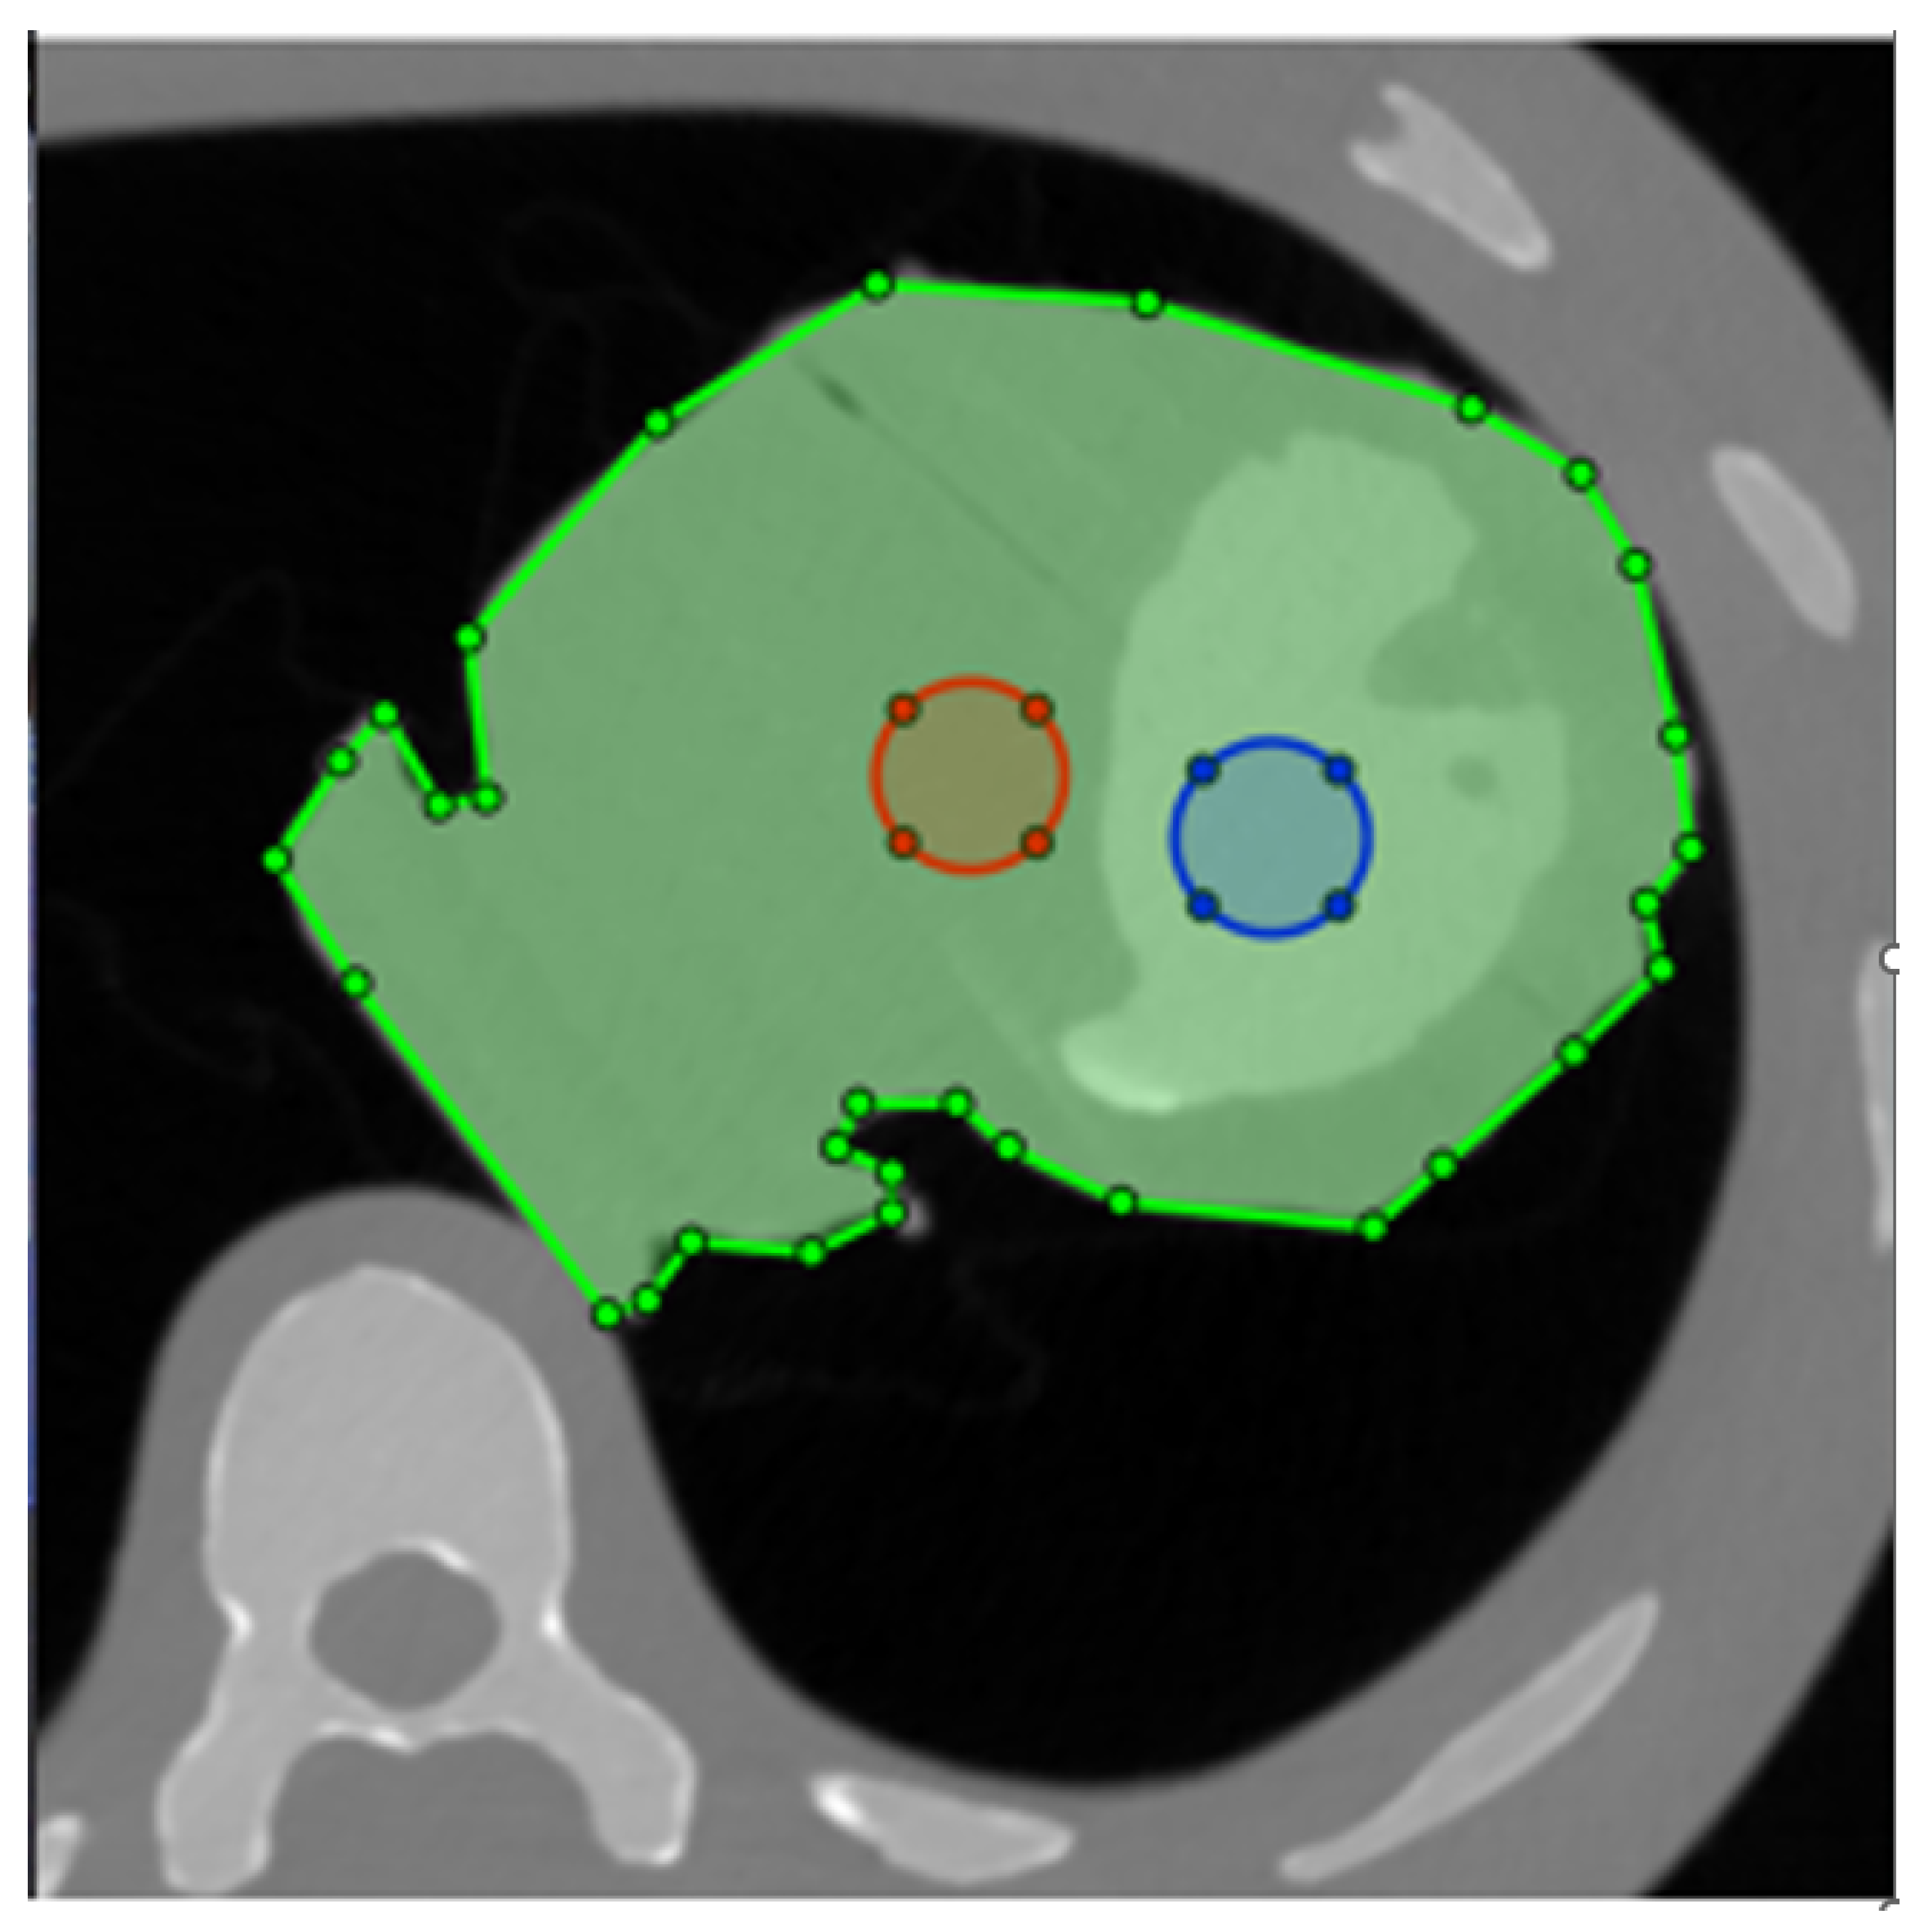

As LV-to-myocardium differentiation relies on differences in Hounsfield Units (HU) between myocardium and contrast, we calculated the CNR between the phantom LV cavity and the myocardium, whereby two circular ROIs with a diameter of 2 cm were drawn in the phantom LV cavity and “myocardium” as shown in Figure 2. Myocardium-to-LV CNR was calculated as shown in Equation (1) [17]. For the non-simulated images, these values were, of course, constant within the same dose level. The ROIs were automatically propagated to all tested images, eliminating placement variability.

Figure 2. Placement of the two ROIs for contrast-to-noise ratio (CNR) calculation. The phantom is masked with the green ROI, ensuring that the structural similarity index (SSIM) is only calculated for the heart. Blue and red circles are the ROIs used to measure attenuation and noise in the LV and myocardium, respectively.